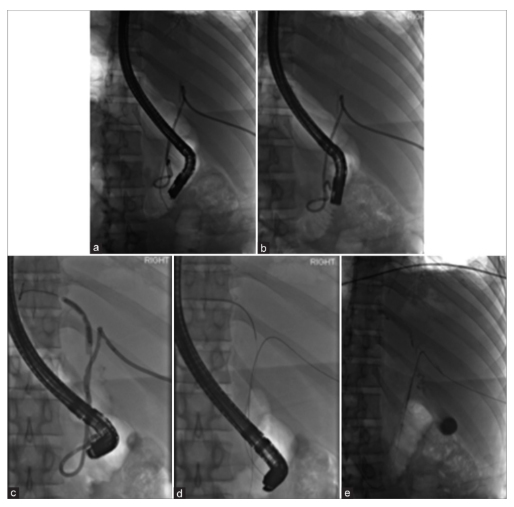

When ERCP fails or is unsafe, LCBDE provides definitive single-stage management, often combined with cholecystectomy.

The transcystic route is usually impractical for intact retained stents due to their length and rigidity. A longitudinal choledochotomy allows controlled extraction and complete ductal inspection.

During biliary surgery, copious saline irrigation is routinely used to clear infected bile and debris. In susceptible patients, this may precipitate acute hydrothorax via Porous Diaphragm Syndrome (PDS).